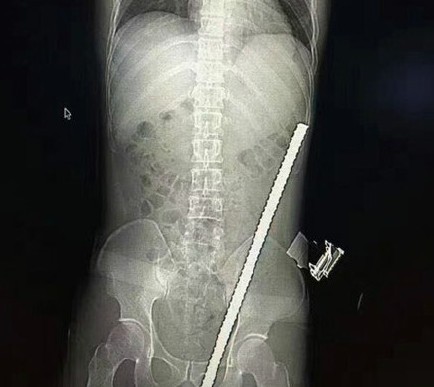

▲鋼筋直插「陰囊」,看圖就覺得痛。(圖/翻攝自人民網微博,下同)

泌尿外科醫師表示,鋼筋是從吳強的陰囊插入,初步估算鋼筋約有50至60公分長,可能傷到睪丸、膀胱、腸道等器官。但X光結果出爐後令人鬆一口氣,醫師表示,這根鋼筋猶如神助,「長了眼睛」,雖然穿透腹壁,但是沿著膀胱邊上穿上去,避開所有危險處,生殖器官、臟器也沒有受到重大損害。

報導指出,手術進行約1小時,將鋼筋從下體緩緩抽出,反覆灌入雙氧水、生理食鹽水沖洗,最後大功告成,患者恢復狀況也很不錯,預計在醫院休養一周後,即可康復出院。